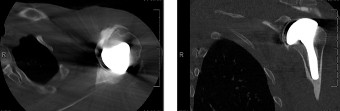

- CT Scan: Valuable for assessing bone loss, especially glenoid vault integrity, prior hardware, and planning for complex revisions.

Figure 1: Pre-operative planning image, potentially demonstrating an X-ray or CT reconstruction used to assess bone loss and guide implant selection for revision surgery.